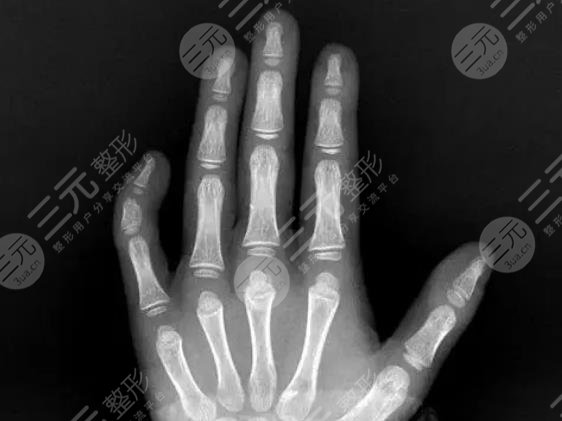

小指彎曲可以整形嗎?在如今較為成熟的整形技術(shù)基礎(chǔ)之上,如果出現(xiàn)小指彎曲,自然是可以進行適當改良的。小指出現(xiàn)彎曲,除了與先天性的因素有著緊密關(guān)聯(lián)以外,后期的環(huán)境或是其他原因所致,可以根據(jù)實際的彎曲程度,選擇合適的手術(shù)方式。當然如果小指出現(xiàn)嚴重彎曲,甚至是影響到整體的外觀,或者是基本的生理功能,自然是可以選擇整形項目。那么究竟小指彎曲是如何通過整形手術(shù)方式改良的呢?以下文章為大家詳細介紹。

利用整形手術(shù)改良彎曲的小指自然是比較可行的,但是需要建立在規(guī)范的醫(yī)生技術(shù)基礎(chǔ)之上,根據(jù)不同原因引起的現(xiàn)象,選擇合適的矯正方式,需要對整個小指進行明確診斷,然后再按照手術(shù)或者是非手術(shù)的緩解方式來進行改良。有些人群的小手指彎曲,由于先天性的遺傳因素出現(xiàn)骨折或是關(guān)節(jié)炎癥,那么則需要進行手術(shù)緩解。

如果是由于燙傷或者是其他的環(huán)境因素導(dǎo)致瘢痕萎縮而引起的小室彎曲,可以利用瘢痕切除等方式調(diào)整即可。雖說現(xiàn)在的整形技術(shù)比較真實,但是如果你想要改良整個小指的彎曲現(xiàn)象,不僅要完善整個術(shù)前的檢查,也需要對整個小指頭的關(guān)節(jié)部位進行適當?shù)姆治?,因此建議求美者應(yīng)當選擇一家正規(guī)性的醫(yī)療機構(gòu)進行實際操作。